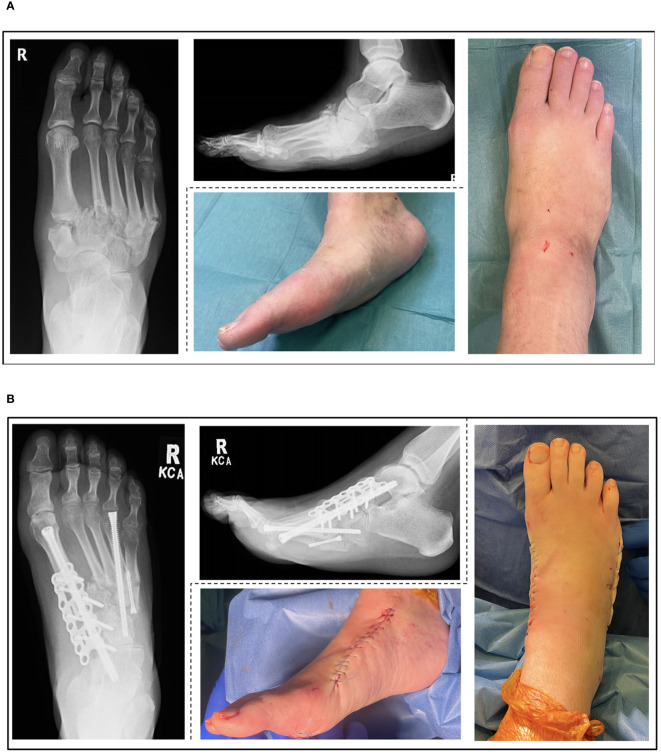

Charcot neuro-osteoarthropathy (CNO), mainly as a result of diabetic neuropathy, is a complex problem which carries significant morbidity, and is an increasing burden on healthcare as demographics change globally. A multi-disciplinary team (MDT) is necessary to treat the multiple facets of this disease. The multifactorial and non-homogenous nature of this condition and its management, has prevented the development of comprehensive guidelines based on level 1 evidence. Although there is a trend to surgically treat these patients in tertiary centres, the increasing prevalence of CNO necessitates the capability of all units to manage this condition to an extent locally. This article conducted a thorough literature search of Pubmed and Embase from 2003 to 2023 including the following search terms; "Charcot" "neuroarthropathy" "diabetic foot" "management" "surgery" "treatment" "reconstruction". The results of this review have been summarised and synthesised into an evidence-based algorithm to aid in the surgical decision-making process, and improve the understanding of surgical management by the whole MDT.